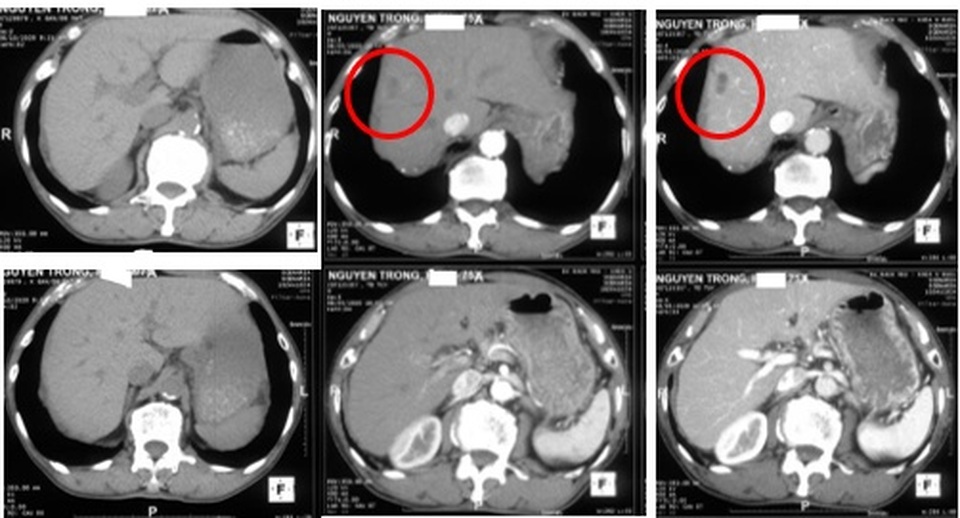

Hình ảnh chụp cắt lớp vi tính ổ bụng cho thấy có khối u trong gan phải.

Kết quả chụp cắt lớp vi tính ổ bụng cho thấy hình ảnh u gan kích thước 25x19mm. Xét nghiệm sán lá gan lớn huyết thanh âm tính, tìm ký sinh trùng trong phân cũng không có.